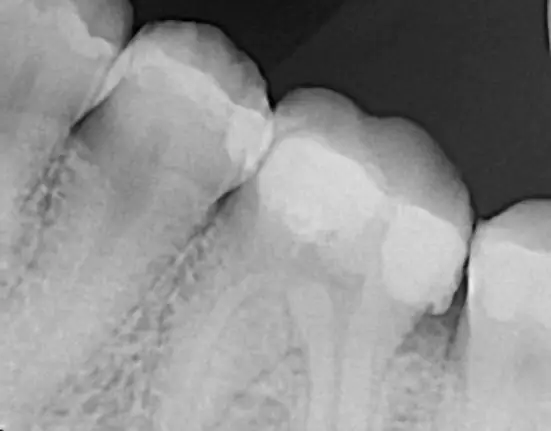

When taking the CBCT for implant placement at sites #19, #30, and #5, we discovered a periapical radiolucency on a previously treated #4. This discovery altered our treatment plan. We paused maxillary implant placement and moved forward with #19 and #30. An endodontic consult revealed a poor prognosis for retreatment of #4, so we extracted it and placed a bone graft with a membrane. During the healing period, we addressed the patient’s other crown needs, which are not all shown in the photos below.

Sites #19 and #30 were uncovered, and restorations are being fabricated at the lab. Meanwhile, sites #4 and #5 have implants integrating, waiting for the next student to uncover and restore. This case reinforced a crucial lesson—great treatment planning isn’t just about following protocol; it’s about seeing the bigger picture and making decisions that will serve the patient for years to come.